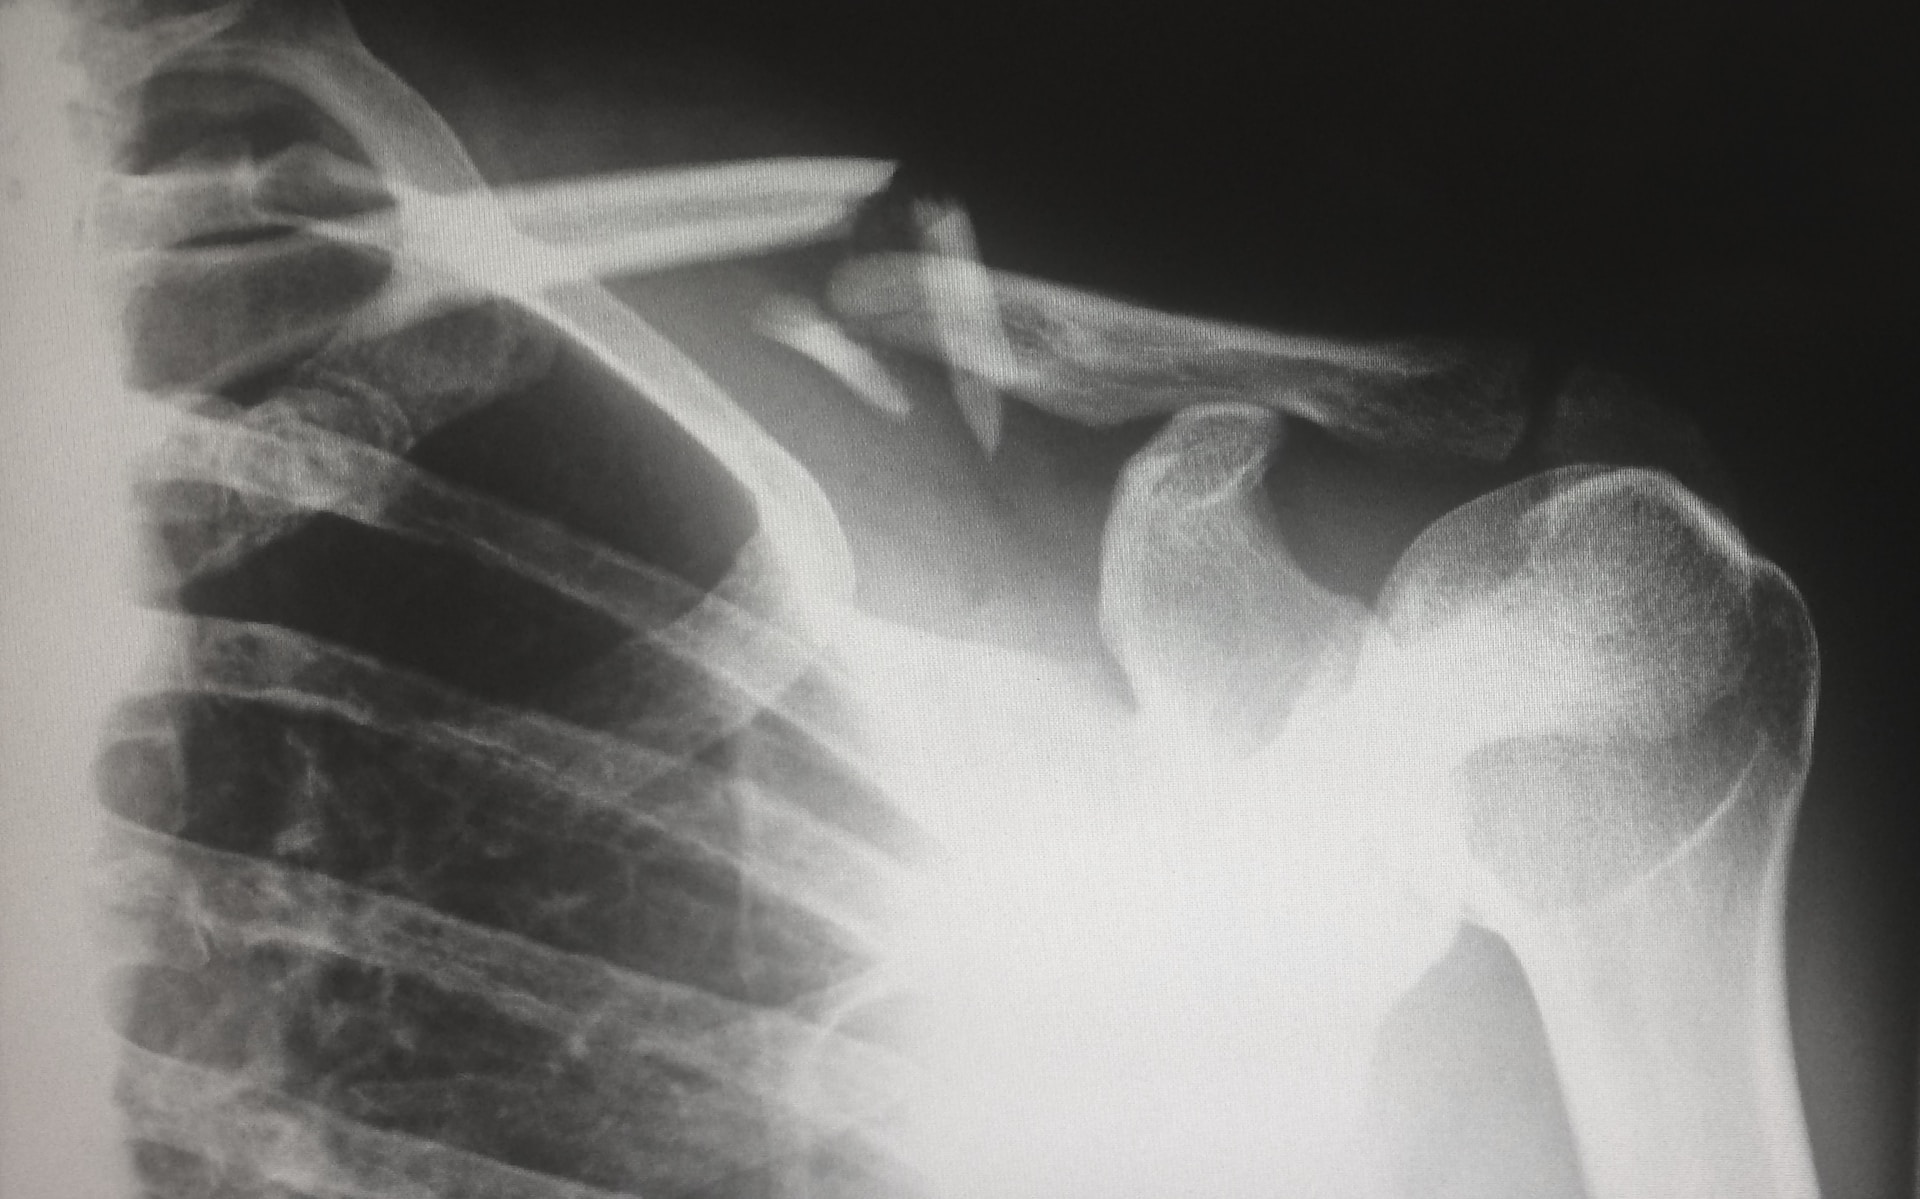

골다공증은 뼈의 밀도가 감소하여 뼈가 취약해지는 상태를 나타내며, 골절의 위험이 증가하며 이는 특히 골다공증으로 올 수 있는 골절 중에서 골밀도 검사를 통해 조기에 발견할 수 있는 경추와 대퇴부 골절이 중요합니다. 이러한 골절은 일상 생활에서 발생할 수 있으며, 더 나아가 심각한 건강 문제로 이어질 수 있습니다.

여성의 골다공증에 관한 중요한 점은 이 질병이 뚜렷한 증상 없이 진행될 수 있다는 것입니다. 때문에 뼈 손실이 진행되어 실제로 골절이 발생하기 전에는 증상이 거의 나타나지 않을 수 있습니다. 그러나 뼈의 밀도 감소로 인해 골다공증이 진행될 경우, 실제로 골절의 위험이 크게 증가하게 됩니다.

골다공증은 주로 골밀도 측정을 통해 진단됩니다. 이는 X선과 같은 방사선 검사로 측정되며, 특히 이중 에너지 X선 흡수측정(DEXA)이라고 불리는 방법이 일반적으로 사용됩니다.